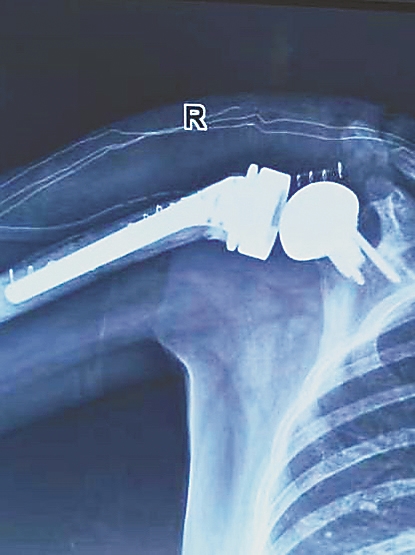

生活报讯 (记者周琳) 4月17日,哈医大一院骨科学科带头人王文波教授在群力院区完成黑龙江省首例反向全肩关节置换术,这也是完成全省首例全肩关节置换。

王文波教授团队择期为李女士进行二期反向全肩关节置换术,最大程度保留肩关节活动度,恢复李女士的肩关节活动度及稳定性。术后,经过康复训练,如今的李女士已能自己完成洗脸洗头、刷牙喝水等基本的日常活动。

王文波教授介绍,“反向全肩关节置换术能有效地恢复肩关节活动度及稳定性,适用于难治性巨大肩袖撕裂、肱骨近端粉碎性骨折、肩关节感染或创伤后骨关节炎、肱骨近端骨肿瘤等疾病的晚期功能重建。与其他手术方式相比,反向全肩关节置换术能很大程度保留肩关节活动度,提升患者生活质量,是患有严重肩关节疾病患者较为合理的治疗选择。”